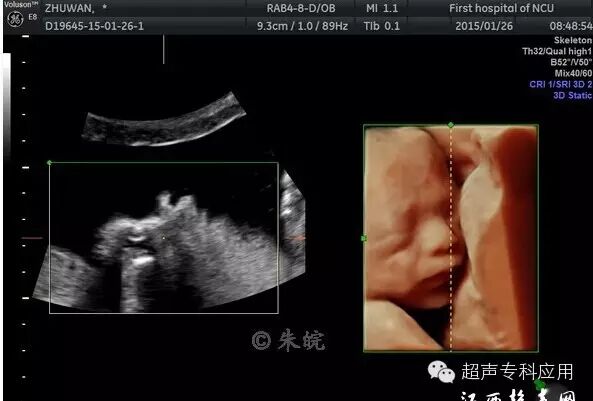

1.1 表面结构的成像 这是三维超声最初在胎儿显像的应用。早孕期可显示整个胎儿的形态以及头颅、腹壁、四肢等;中孕期则能显示胎儿头面部、手指(脚趾)等相对细小的结构。这些表面结构的三维图像,客观逼真,一旦存在胎儿体表的畸形,如唇裂、脑膨出、脊柱裂、脐膨出、腹裂、肢体或手脚畸形,三维成像能够让孕妇及家属一目了然,让产科医生或儿科医生更结合实际情况进行咨询,方便选择下一步的处理方案。虽然三维超声对体表畸形的诊断可能并不比二维超声提供更多信息,这些体表畸形可能在二维声像图上也较容易显示,但孕妇及家属却不理解二维图像,难以想象畸形外观如何、有多严重。为了更人性化的服务,目前,也有不少医院或产院对孕妇提供“胎儿照相”;四维超声观看胎儿运动并录像,以留作纪念。三维表面成像的重要条件是感兴趣区域前方一定要有足够的羊水,而且不能被肢体、脐带等遮挡。羊水过少或晚孕期胎儿充满官腔时,三维表面成像则有较大困难。

胎儿唇裂表面三维成像